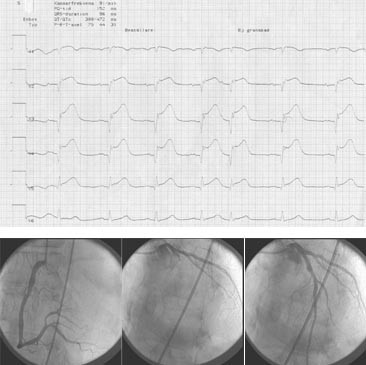

Diameter på innfører i femoralarterien var 8 F (2,7 cm) hos 89 %, 7 F hos 9 % og 6 F hos 2 % (tab 1). Denne ble trukket ut samme dag hos 23 % og ble liggende inne til neste dag hos 77 %. Planlagt strategi var angiografi av antatt frisk arterie først og deretter angiografi og angioplastikk av den infarktrelaterte arterien (fig 1). Dette ble gjennomført hos 77 %. På grunnlag av EKG og angiografifunn var vi i stand til å identifisere aktuelle okkluderte arterie hos 97 %, mens hos de øvrige 3 % måtte vi åpne mer enn ett kar. Tiden som gikk med på laboratoriet fremgår av tabell 1.

Fordelingen av graden av koronararteriesykdom var ettkarsykdom hos 55 %, tokar- hos 25 % og trekar- hos 20 % (tab 1). Tabell 2 viser angiografiske funn i den infarktrelaterte arterien. 85 % var helt eller nærmest helt okkludert og i 92 % var det lite eller ingen antegrad blodstrøm. Synlig trombe eller sterk mistanke om trombe ble funnet hos 69 %. Infarktlesjonen omfattet avgangen av store sidegrener hos 12 %.

Den infarktrelaterte arterien ble åpnet med godt resultat hos 95 % (tab 2). Hele 87 pasienter hadde normal blodstrøm i den infarktrelaterte arterie (TIMI 3) og ytterligere seks pasienter hadde god antegrad blodstrøm, men noe langsommere utvasking av kontrasten enn normalt (TIMI 2). Totalt 14 pasienter hadde resttromber enten lokalt ved stenosen eller perifert i arterien ved avsluttet prosedyre. Av disse fikk halvparten platehemmeren GPIIb/IIIa.